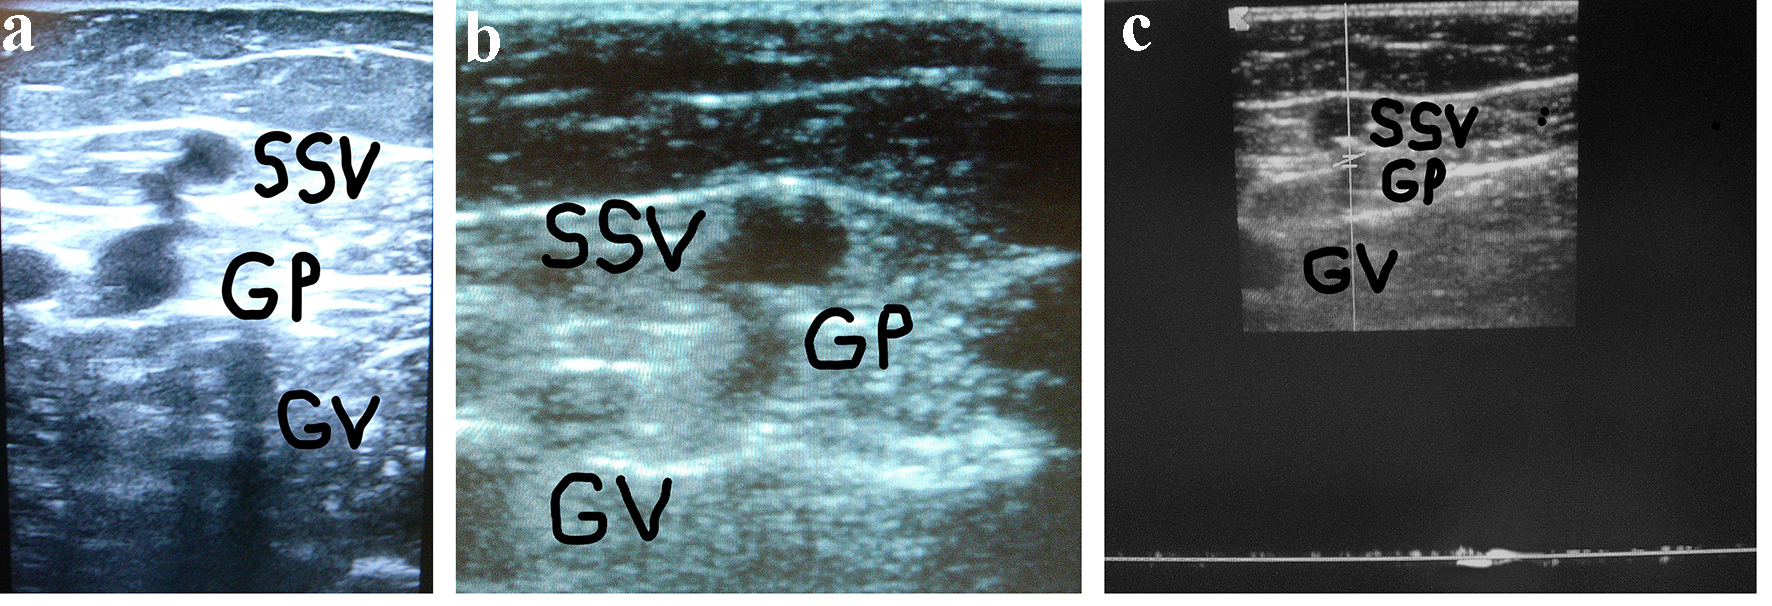

In the 17 treated limbs, a successful clinical and DUS outcome was obtained and no residual sources of reflux were detected. One example of the combination of surgery and sclerotherapy is shown in Figure 1. In 12 limbs subjected to surgical revision and intraoperative foam sclerotherapy and in the four cases subjected to DUS-guided foam sclerotherapy, a complete fibrotic occlusion of the SSV was found at the DUS follow-up (statistically unparsable).

![]() Click for large image | Figure 1. (a) A woman of 67 years of age. Appearance of symptomatic VR in the PR 4 years after the previous surgical procedure for varicose veins at the PR. Cross scanning of DUS examination at the PR: incompetent gastrocnemius perforator (GP) connected with the long residual SSV stump. The internal gastrocnemius vein (GV) is visible. (b) Treatment: SPJ surgical interruption and intraoperative DUS-guided foam sclerotherapy of gastrocnemius perforator (GP) and residual SSV. DUS examination after 30 days: the SS stump is not compressible and partially hyper-echogenic from early fibrosis (SSV), the gastrocnemius perforator (GP) is hyper-echogenic from early complete fibrosis in the subfascial segment, the internal gastrocnemius vein (GV) is patent and compressible. (c) DUS examination after 30 days: the gastrocnemius perforator (GP) is occluded with no flow into the lumen, the SS stump is not compressible and hyper-echogenic from advanced fibrosis (SSV), the internal gastrocnemius vein (GV) is patent and compressible. |